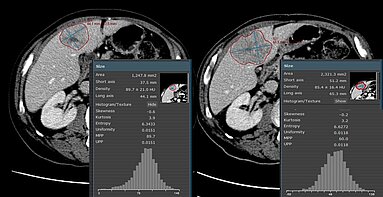

University Hospital Tübingen: Study shows prediction power of clinical and CT imaging biomarkers

A recent retrospective study [1] conducted by researchers at University Hospital Tuebingen focused on identifying imaging and clinical predictors of overall survival and treatment response in…